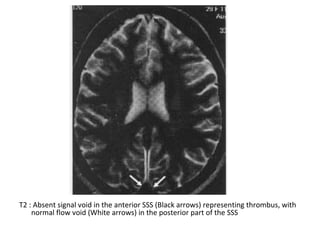

T2 : Absent signal void in the anterior SSS (Black arrows) representing thrombus, with

normal flow void (White arrows) in the posterior part of the SSS